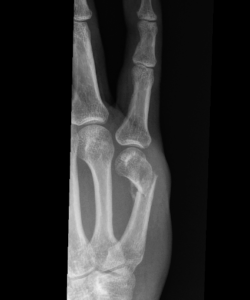

X-rays: to identify fracture location, displacement, and joint involvement

Surgical Treatment of Finger Fractures

Below are examples of surgical treatment options. Each depend on the fracture type.